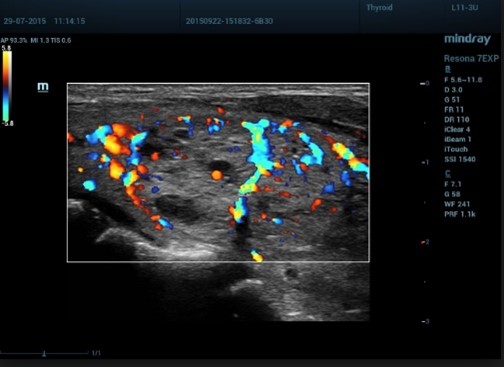

Λογισμικό Ελαστογραφίας STE shearwave Elastography (optional)

Η προσφερόμενη μονάδα υπερήχων παρέχει την πιο σύγχρονη και πρωτοποριακή απεικονιστική τεχνική Shearwave Elastography STE για την μη επεμβατική ιστική μελέτη επιφανειακών και ενδοκοιλιακών οργάνων. Διαθέτει διπλή και ταυτόχρονη απεικόνιση (Real Time) 2D & 2D + ελαστογραφία shearwave με χρωματική κωδικοποίηση των ιστών (προς επιλογή διαφορους ελαστογραφικούς χάρτες). Η μέθοδος χρησιμοποιείται για την μελέτη αλλοιώσεων σε επιφανειακές και εν τω βάθει δομές όπως στον προστάτη, μικρά όργανα άνω κάτω κοιλία κλπ. Η υπερηχογραφική Ελαστογραφία παρέχει στον κλινικό ιατρό πληροφορίες υψηλής ευαισθησίας και ειδικότητας για την ελαστικότητα των ιστών εφοδιάζοντάς τον με πληροφορίες που τον βοηθούν στον χαρακτηρισμό και την κατηγοριοποίηση των ιστολογικών αλλοιώσεων.

NTE (optional)

Σύγχρονη τεχνική ελαστογραφίας για τον διαχωρισμό μεταξύ μαλακών (ελαστικών) και σκληρών (συμπαγών) ιστών, σε κλινικές εφαρμογές μαστού και θυρεοειδούς. Διαθέτει διπλές ταυτόχρονες απεικονίσεις 2D & 2D+ ελαστογραφία με χρωματική κωδικοποίηση των ιστών (8 ελαστογραφικούς χάρτες) σε Real Time (πραγματικό χρόνο). Η μέθοδος Strain elastography NTE Natural touch elastography είναι μέθοδος μέτρησης της ελαστικότητας και της σκληρότητας των ιστών που χρησιμοποιείται για την μελέτη αλλοιώσεων σε επιφανειακές δομές όπως στο μαστό, θυρεοειδή που συσχετίζονται με την αλλαγή της σκληρότητας των ιστών. Η υπερηχογραφική Ελαστογραφία παρέχει στον κλινικό ιατρό πληροφορίες υψηλής ευαισθησίας και ειδικότητας για την ελαστικότητα των ιστών εφοδιάζοντάς τον με πληροφορίες που τον βοηθούν στον χαρακτηρισμό μιας βλάβης, επιλογή μεταξύ διαφορετικών χαρτών και δυνατότητα μετρήσεων STRAIN RATIO MEASUREMENT.